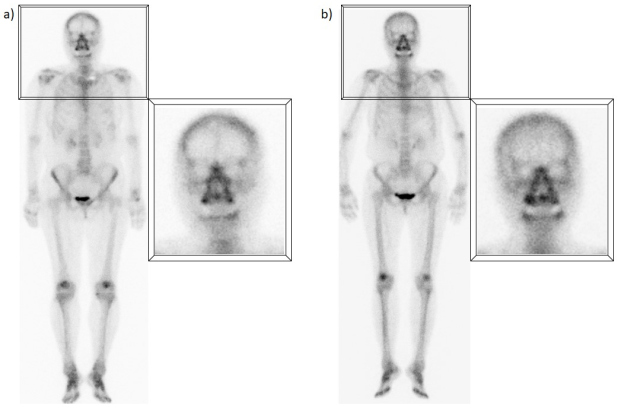

B) Captación occipital en la línea media

Suele presentarse en la proyección de la protuberancia occipital externa, prominencia ósea donde se insertan el ligamento nucal y el músculo trapecio. Estos músculos prominentes expuestos a una alta sobrecarga constante pueden sufrir inflamación crónica y gradual, con la consecuente formación de exostosis por tracción, lo que explica el aumento focal de la captación en la gammagrafía ósea. Estudios recientes han demostrado la relación de este hallazgo con el uso de dispositivos electrónicos, especialmente en adolescentes y adultos jóvenes, que al asociarse a periodos prolongados de hiperflexión del cuello puede originar sobrecarga de estas estructuras musculares(3) (fig. 2).